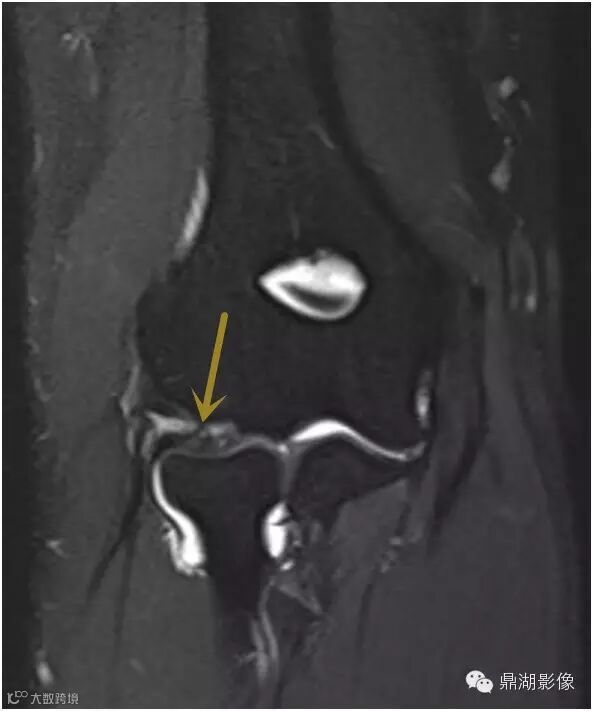

抑脂序列冠状位及矢状位T2WI显示在后外侧肱桡关节间隙内增厚的滑膜皱襞隆起并折叠(箭头)。

皱襞内可见高信号影,测量超过3毫米的厚度,并覆盖了几乎一半的桡骨头关节面。并可见易被误认为是肱骨小头缺损的正常肱骨头(*)。